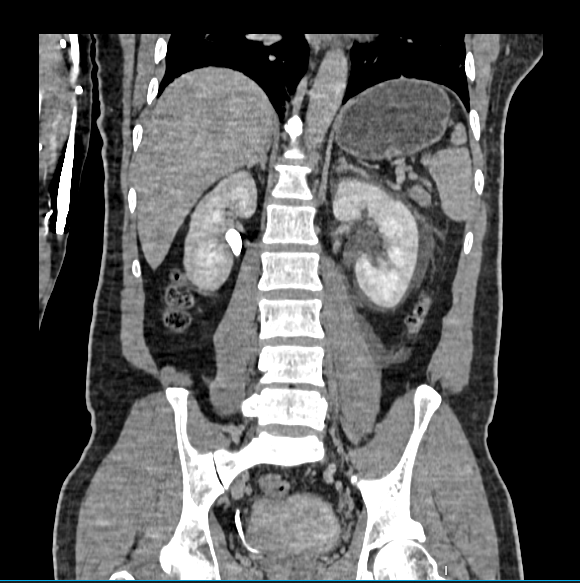

Right Kidney

- Size: Measures 10 x 4.9 cm.

- Pelvicalyceal System: Not dilated.

- Enhancement: Homogeneous enhancement during the nephrogenic phase.

- Ureter: Not dilated; no calculus seen.

- Vesico-Ureteric Junction: Appears normal.

Left Kidney

- Size: Measures 11 x 4.7 cm.

- Calculus: Small calculus of size approximately 3.2 x 3 mm at the left vesico-ureteric junction, causing mild hydroureteronephrosis.

- Urothelial Thickening: Hyperenhancement involving renal pelvis and ureter, suggestive of acute pyelo-ureteritis.

- Perinephric Findings: Fat stranding, Gerota’s fascia thickening, and mild perinephric fluid collection.